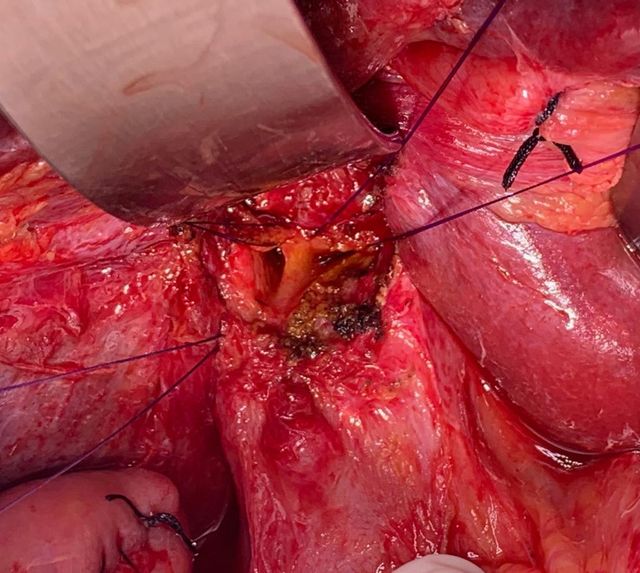

Challenging emergency during the COVID: Child’s A CLD with HUGE gastric varices uncontrolled

Child’s A CLD with HUGE gastric varices uncontrolled by Endoscopic glue and attempted EUS coiling. One salvage option would be TIPSS with balloon vascular occlusion but due to logistics we went for modified sugiura procedure. Splenectomy + Gastro esophageal devascularisation with anterior Gastrotomy and overseeing of gastric varices with pyloroplasty. Images show 1 CECT showing large gastric fundal varices. 2,3,4 Gastro Esophageal devasc 5, 6 Large fundal varices before and after oversewing. 7. Anterior gastrotomy 8. Pyloroplasty. Postoperative recovery was uneventful.